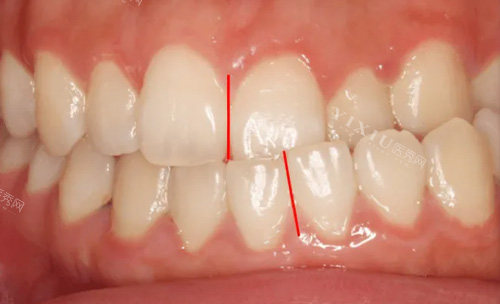

骨性嘴凸主要表现为上颌前突或下颌后缩,导致嘴唇无法自然闭合。与单纯牙齿不齐不同,这种问题涉及颌骨发育异常,需要早期干预才能取得理想结果。